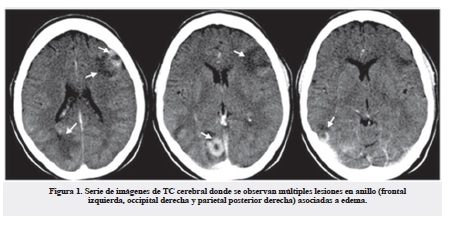

Al séptimo día del ingreso comenzó con crisis focales simples mioclónicas que involucraron el miembro superior derecho, lo que motivó una interconsulta con neurología. En el examen físico neurológico no se constataron signos focales ni papiledema. Se decidió realizar una TC cerebral donde se observaron múltiples lesiones en anillo (frontal izquierda, occipital derecha y parietal posterior derecha) asociadas a edema, que no desplazaron las estructuras de la línea media ni produjeron herniaciones, las cuales captaron poco contraste en la periferia en estudio de TC contrastada (Figura 1). Las características imagenológicas de estas lesiones ofrecían la duda diagnóstica entre una infiltración al sistema nervioso central por su enfermedad de base o múltiples abscesos cerebrales.